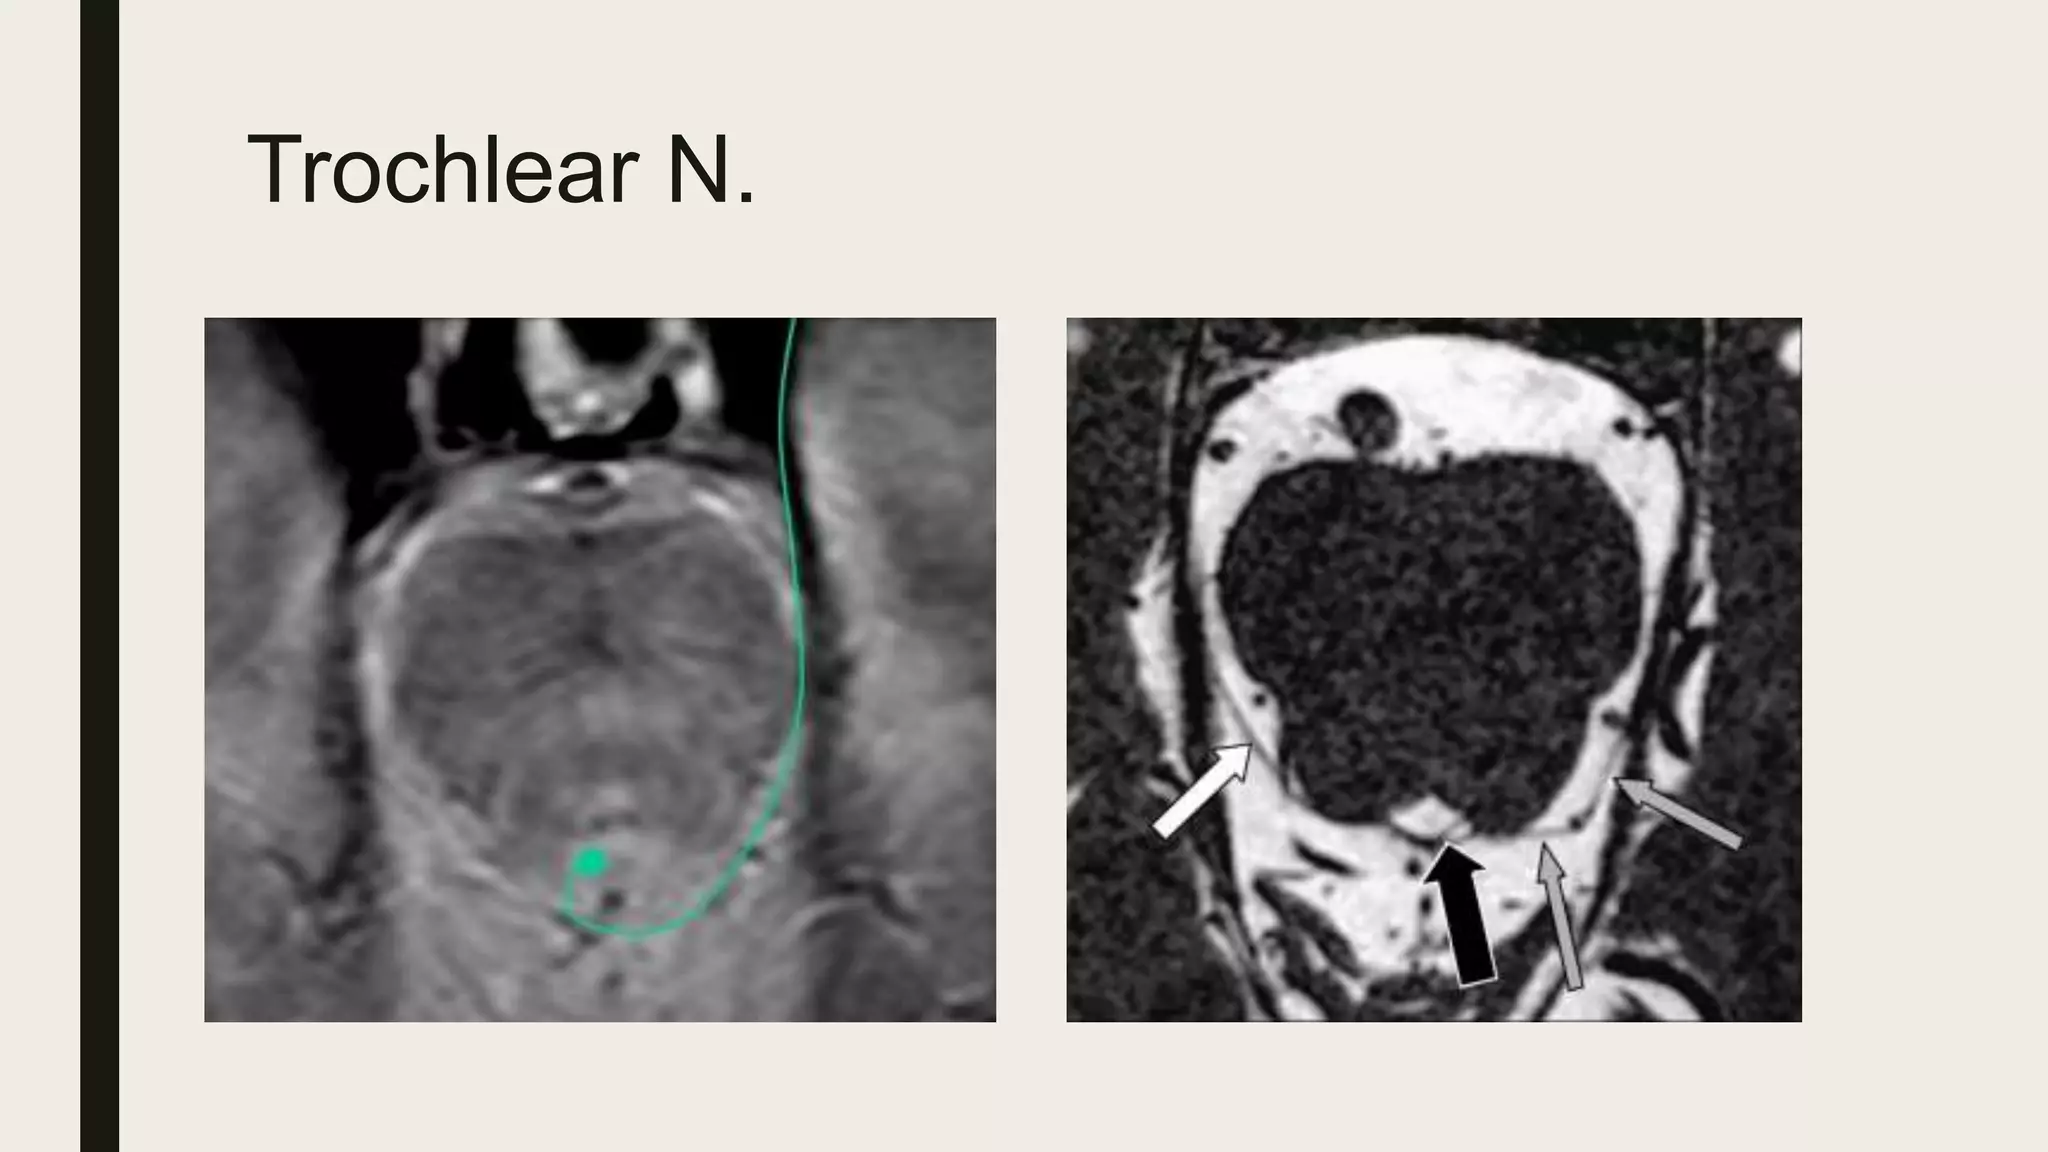

Ambient cisterns

• Ambient = surrounding.

• Extension of the quadrigeminal cistern

lateral to the midbrain.

Location

• P2 segment of PCA.

• SCA.

• AchA.

• Lateral mesencephalic V.

• Basal vein of Rosenthal .

• CV IV.

Contents

Trochlear N.